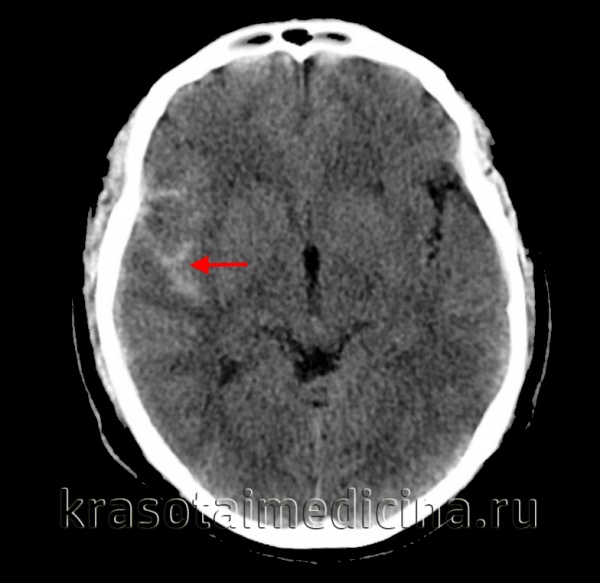

(а) Бесконтрастная КТ, аксиальный срез: в нескольких бороздах и в межножковой цистернах определяется скопление гиперденсной крови вследствие травматического субархноидального кровоизлияния (тСАК).

(б) MPT, FLAIR, аксиальный срез: определяется аномальный гиперинтенсивный сигнал от СМЖ, расположенной в межножковой, а также обводной/четверохолмной цистернах. Также выявляется небольшое количество крови в гравитационно зависимом отделе правого лобного рога бокового желудочка. (а) MPT, FAIR, аксиальный срез: от СМЖ правой сильвиевой щели, а также в нескольких бороздах правого полушария определяется аномальный гиперинтенсивный сигнал, соответствующий травматическому субарахноидальному кровоизлиянию (тСАК).

(б) Бесконтрастная КТ, аксиальный срез: двустороннее расширение борозд (больше справа) за счет скопления изоденсной ликвору крови (подострая-хроническая стадия САК).